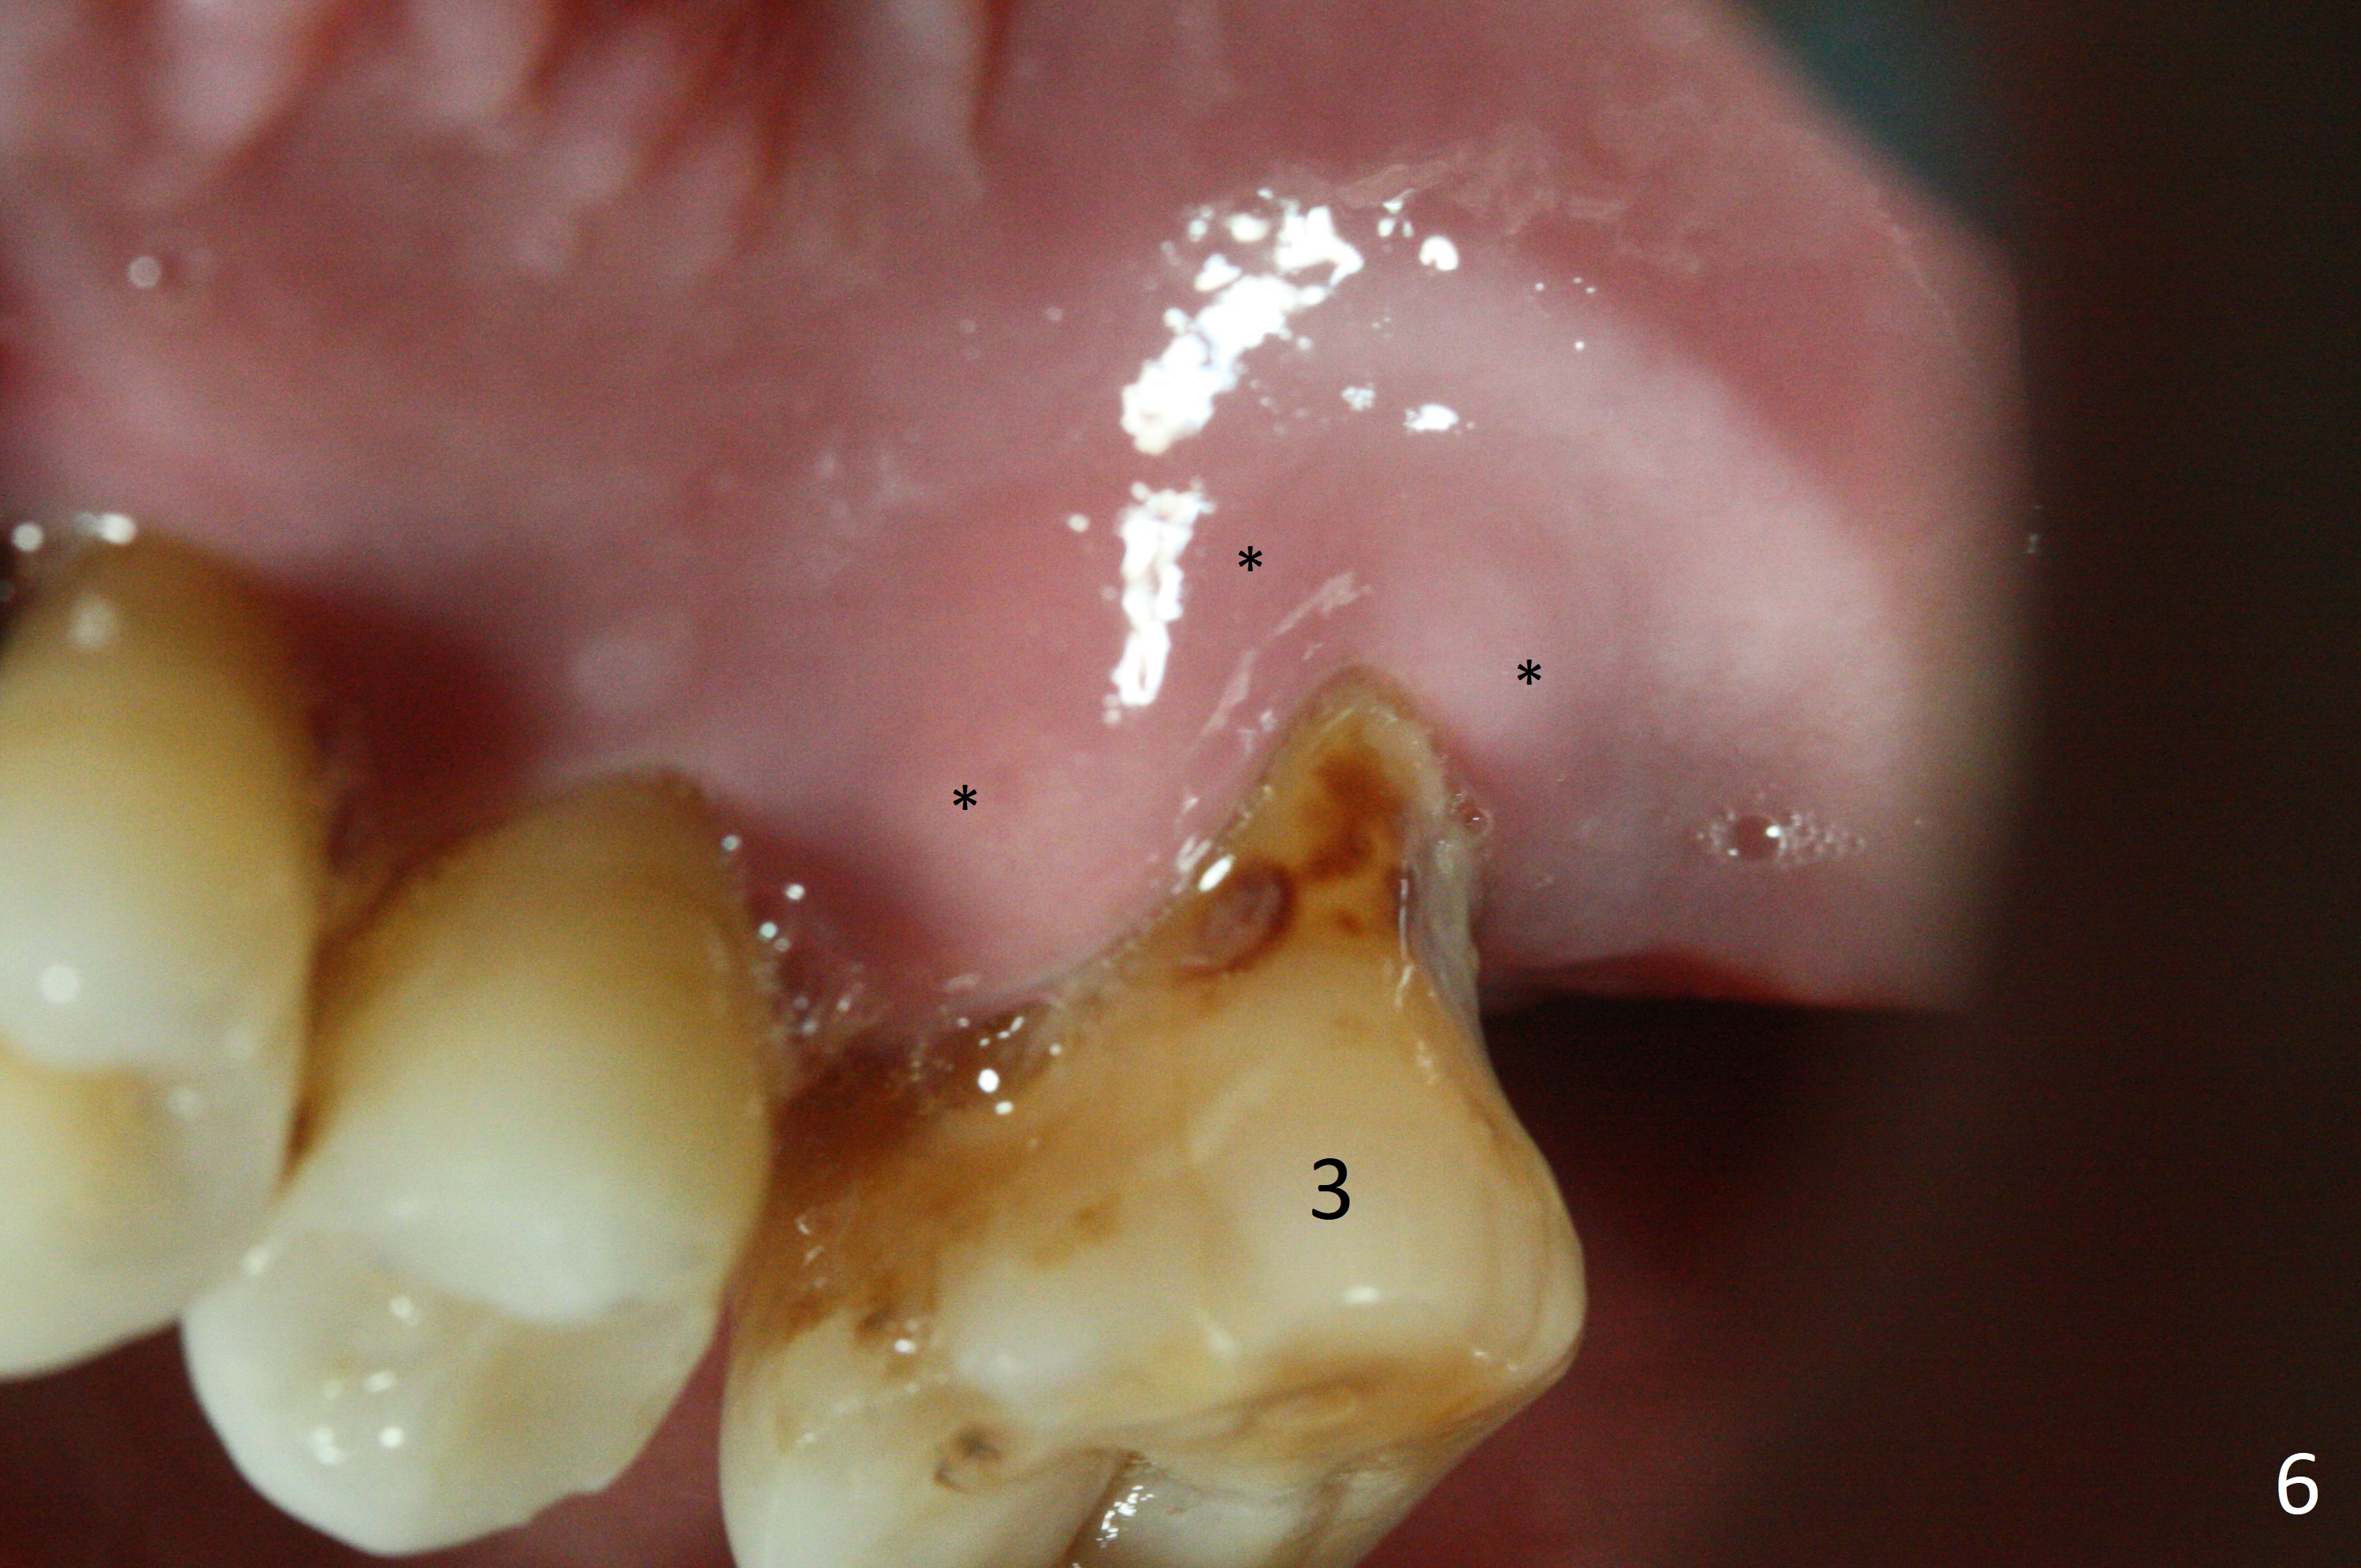

Recently periodontal abscess occurs with purulent discharge from the buccal sulcus (Fig.5 *) and palatal gingiva erythema and edema (Fig.6 *). The buccal and palatal plates are most likely defective. A small diameter implant should be placed. The infection at #3 may be the cause of failure of implant at #31 (redo).